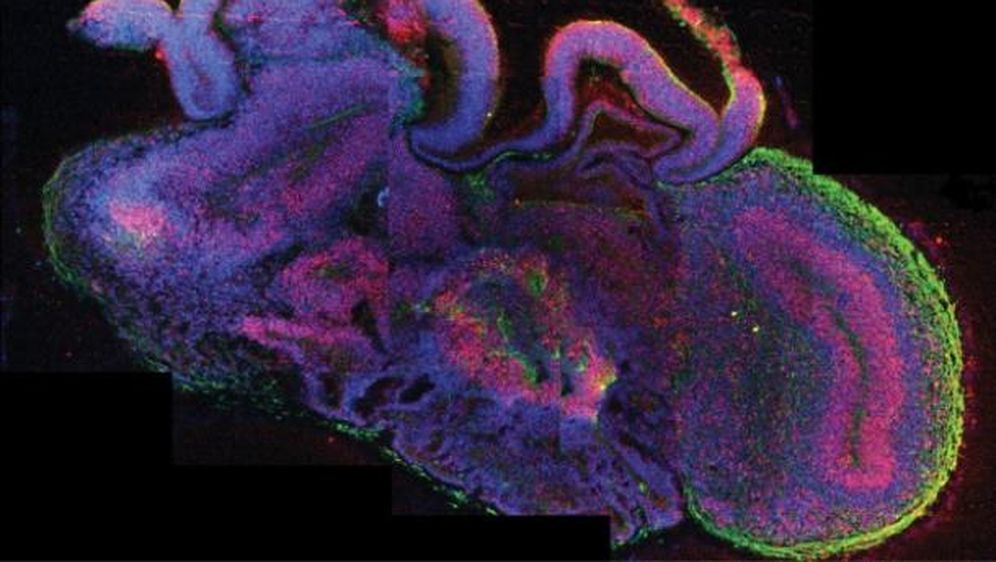

Kako bi shvatili kako funkcionira najkompleksniji ljudski organ, austrijski su znanstvenici u laboratorijima uzgojili su iz matičnih stanica model ljudskog mozga koji sadrži korteks, hipokampus i mrežnicu.